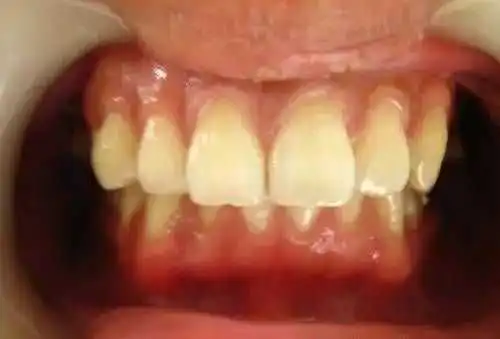

定期洗牙是目前最有效的治疗牙周疾病的方式。下面是洗牙前后的对比图:

洗牙(洁治)后,洁白如一